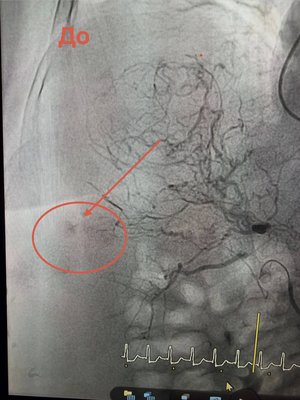

Відкрита операція — неможлива, але завдяки ендоваскулярній хірургії та ангіографії вдалося зупинити кровотечу методом емболізації судини.